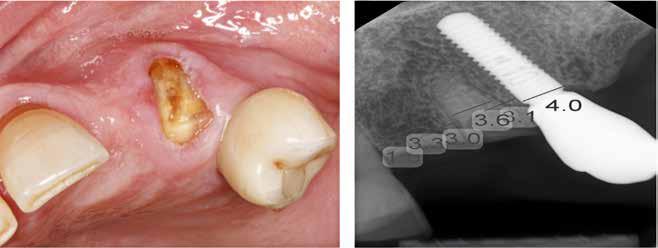

Klik ind på Tandlægebladet.dk og opret en reklamation, så sørger vi for, at bladet lander i din postkasse.

Klik ind på Tandlægebladet.dk og vælg om os

BAGGRUND – Transverselle okklusionsafvigelser kombineret med en vækstbetinget kæbedeformitet korrigeres sædvanligvis ved en sektioneret Le Fort 1-osteotomi eller kirurgisk assisteret ganeekspansion. Ved ekstreme transverselle skeletale diskrepanser mellem maksillen og mandiblen kan der være indikation for transversel udvidelse af mandiblen ved hjælp af mandibulær midtlinjeosteotomi eller mandibulær midtlinjedistraktionsosteogenese.

PATIENTTILFÆLDE – En 15-årig dreng med infantil autisme blev henvist fra Hjørring Kommunes Tandpleje til Kæbekirurgisk Afdeling, Aalborg Universitetshospital, for ortodontisk-kirurgisk behandling af et stort horisontalt maksillært overbid uden kontakt på nogen af tænderne. Den vækstbetingede kæbedeformitet blev korrigeret ved hjælp af ortodonti og mandibulær midtlinjedistraktionsosteogenese efterfulgt af en sektioneret Le Fort I-osteotomi og bilateral sagittal splitosteotomi.

KONKLUSION – Mandibulær midtlinjedistraktionsosteogenese er en forudsigelig behandlingsmodalitet til transversel udvidelse af mandiblen. Imidlertid er behandlingen forbundet med en betydelig risiko for recidiv samt biologiske og tekniske komplikationer, hvorfor mandibulær midtlinjedistraktionsosteogenese udelukkende anbefales til korrektion af ekstreme vækstbetingede transverselle okklusionsafvigelser.

EMNEORD Jaw abnormalities | malocclusion | orthodontics | orthognathic surgery

PERNILLE SAGBAKKEN, tandlæge, Odontologisk Institut, Det Sundhedsvidenskabelige Fakultet, Københavns Universitet

ANNETTE DALGAARD KJELLERUP, specialtandlæge i ortodonti, Kæbekirurgisk Afdeling, Aalborg Universitetshospital